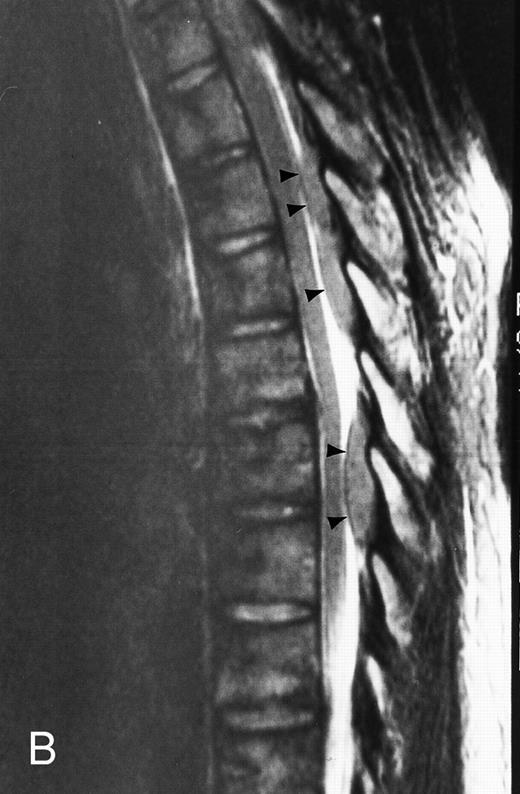

T1-weighted (500/11, TR/TE) sagittal MR images of the lumbosacral spine in a 45-year-old woman before (A) and 40 days after (B) bone marrow transplantation for multiple myeloma. There is a diffuse MR pattern of marrow involvement in (A) (bone marrow plasma cells, 50%; monoclonal protein, 6.0 g/dL). On the posttreatment image, there is definite reinstitution of fatty marrow in the spine and, in particular, around the basivertebral veins, in keeping with partial response to treatment (bone marrow plasma cells, 0.5%; monoclonal protein, 1.6 g/dL).